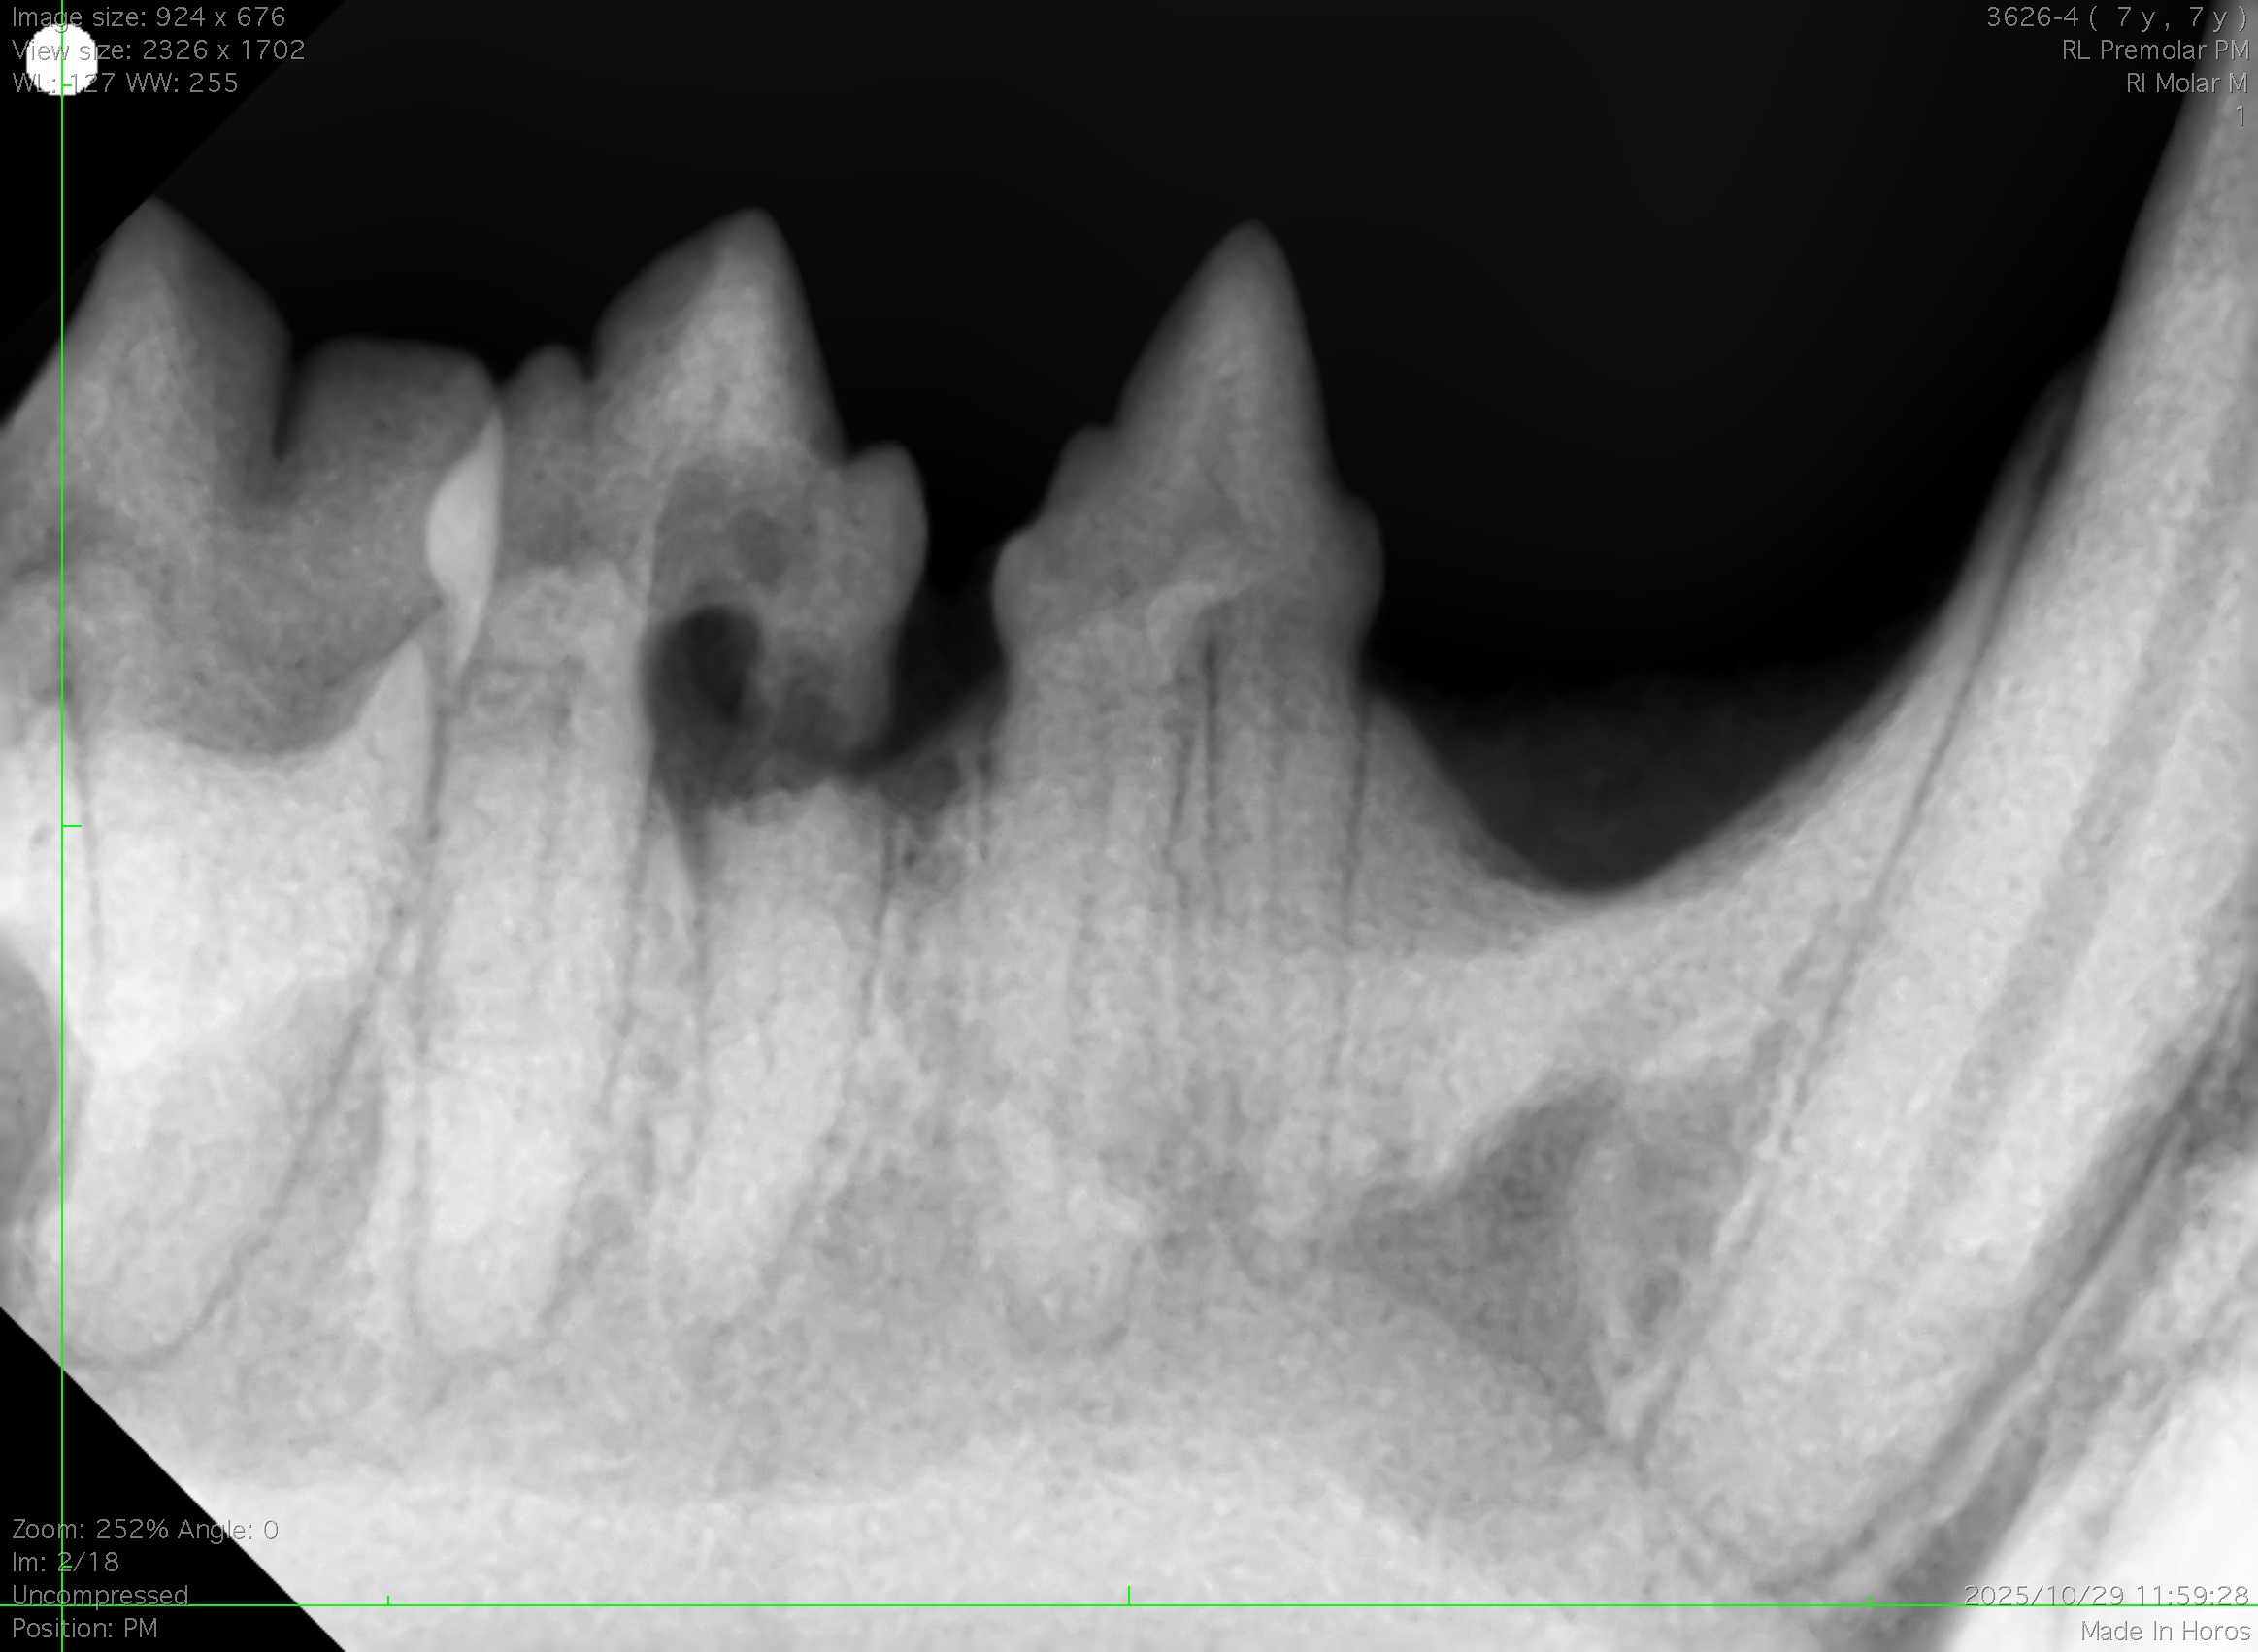

こんにちは! 世田谷区等々力のけいこくの森動物病院です🌳 今回は猫ちゃんで多い「吸収病巣」の症例をご紹介します。 吸収病巣とは? 「吸収病巣(きゅうしゅうびょうそう)」は、正式…